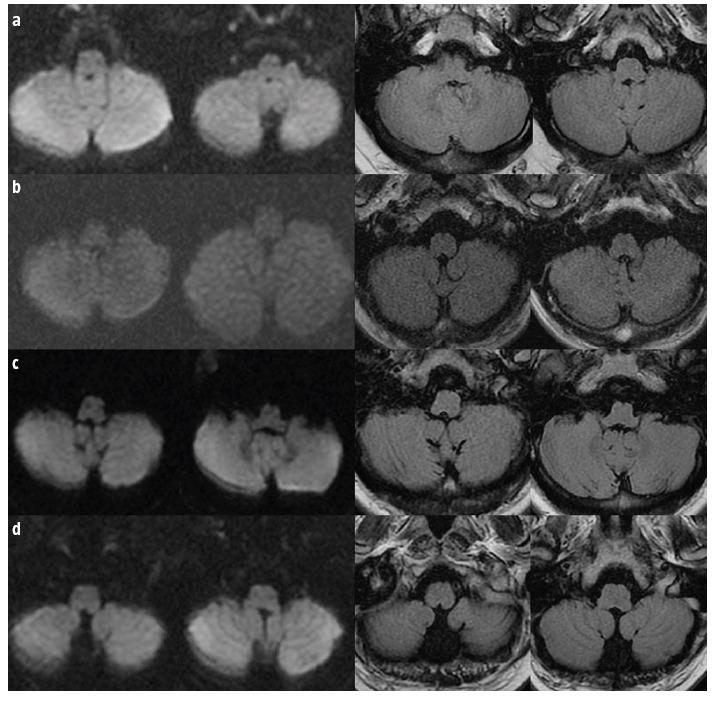

Four patients presented after sudden-onset gait lateropulsion. On neurological examination, all patients had at least one cortical sensory deficit and wide-based gait with lateropulsion towards the side of the cortical deficit. Neuroimaging revealed a subacute parietal lobe stroke contralateral to the side of gait lateropulsion. In two patients we found bilateral lateropulsion with predominance towards the side of cortical deficit and increase of unsteadiness with eye closure (an apparent Romberg sign), with neuroimaging revealing bilateral parietal strokes (subacute contralateral and chronic ipsilateral to gait lateropulsion).

4 例患者出现突发性步态侧方偏倚。在神经学检查中,所有患者均至少存在一处皮质感觉缺失和宽基底步态,并伴有向皮质缺失侧的侧方偏倚。神经影像学显示与步态侧方偏倚侧相对应的亚急性顶叶中风。在 2 例患者中,我们发现双侧侧方偏倚,以皮质缺失侧为主,并伴有闭眼时不稳定性增加(明显的 Romberg 征),神经影像学显示双侧顶叶中风(亚急性对侧和慢性同侧与步态侧方偏倚)。